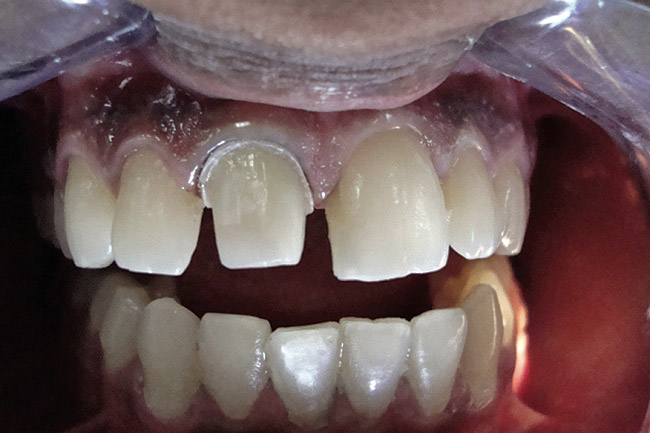

Figure 5  Finish line at the crest of the free gingiva.

Figure 5

Figure 6  Small-diameter cord is first placed in the sulcus.

Figure 6

Figure 7  Large-diameter cord is placed; half its thickness is above small-diameter cord.

Figure 7

Figure 8  Small-diameter cord is left in the sulcus once the larger diameter cord is moistened and removed after 8 to 10 minutes.

Figure 8